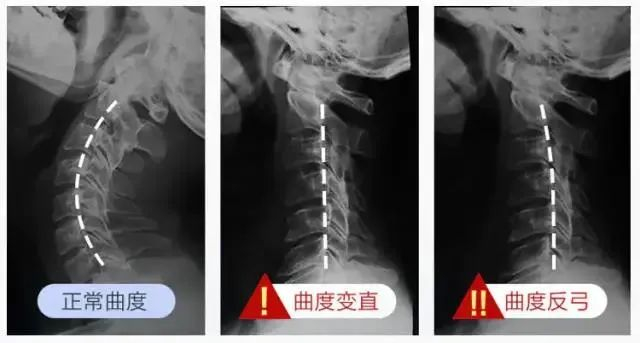

正常人的颈椎,是有一定曲度的。

长期不正姿势颈椎会变直,严重的甚至曲度反弓,进而发展成颈椎病。

大家都知道,正常的颈椎呈 S 型,但长期低头、坐姿不对,出现疼痛还置之不理,就会造成颈椎变直或者反弓。

进而出现脖子僵硬疼痛、颈前曲、驼背等颈椎问题,按摩也无济于事。